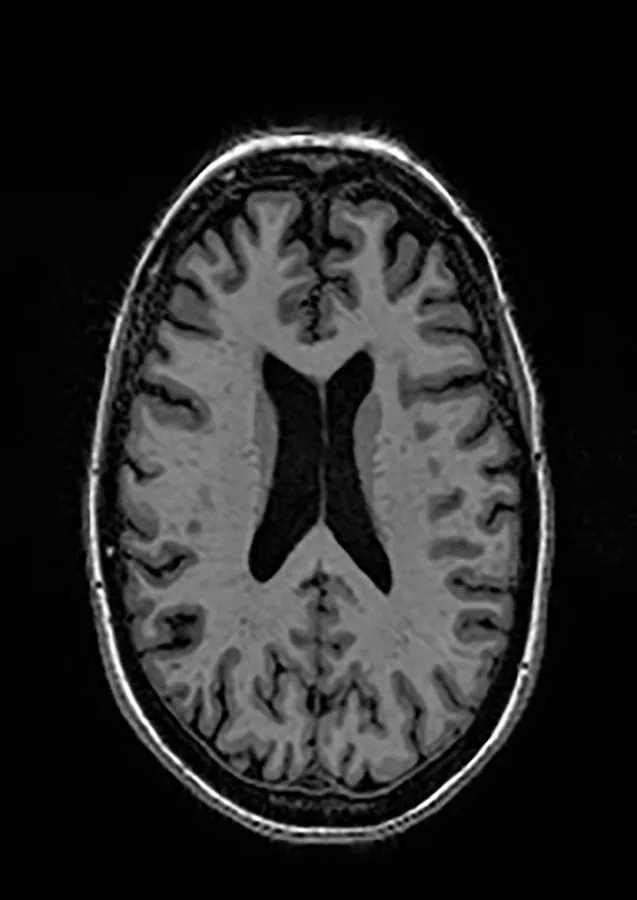

2.2 Datasets

Two different datasets (the Alzheimer’s dataset (four classes of images) and ADNI_Extracted_Axial) were used to validate the proposed approach. Both datasets are publicly available (https://www.kaggle.com/datasets/tourist55/alzheimers-dataset-4-class-of-images and https://www.kaggle.com/datasets/katalniraj/adni-extracted-axial; accessed November 13, 2023). The specifications of this dataset are listed in Table 1.